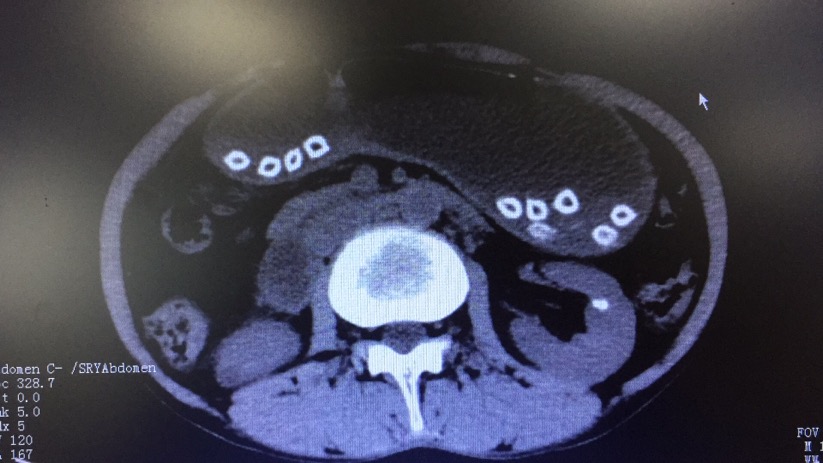

CT结果显示的杨梅核

入院时,谢先生腹部疼痛难忍,腹部CT提示胃内异物,完善术前检查后,张渝副主任医师为谢先生在胃镜下实施异物取出术,通过异物网篮共取出32颗杨梅核,其中有3颗崁顿在十二指肠球部,使得肠壁变薄,有穿孔的危险。